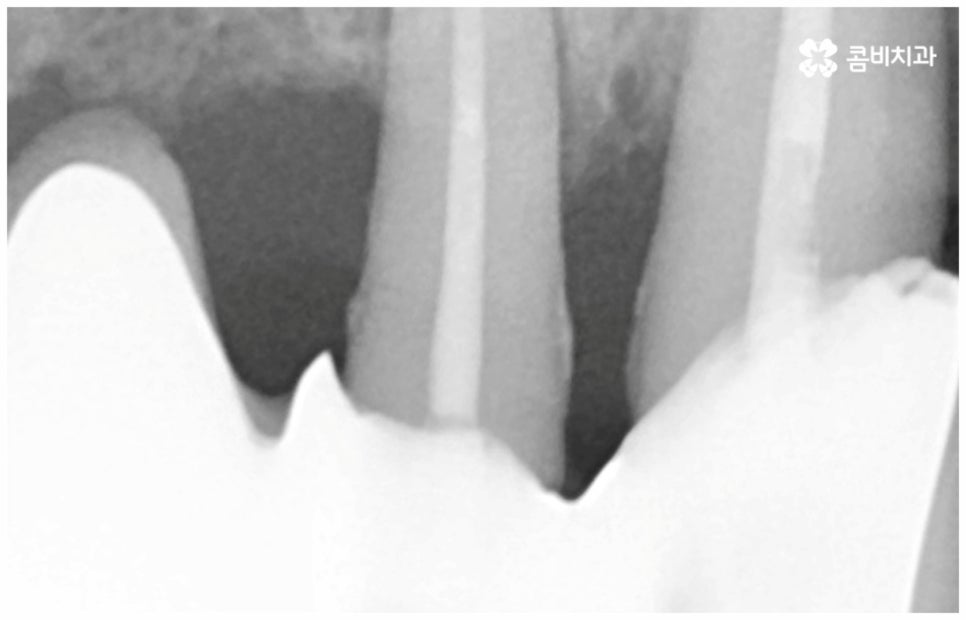

보통 정확한 위치에 식립하고 철저하게 사후 관리를 해 준다면 임플란트수명 은 거의 반영구적이라고 할 정도로 오랫동안 건강하게 사용할 수 있습니다. 그러기 위해서는 처음 식립할 때 환자분들의 상황에 맞게 체계적인 계획을 세워 정밀한 식립을 진행할 수 있는 시술자의 높은 숙련도 외에도 꼼꼼한 검사를 위한 3D-CT 와 같은 정밀 진단 장비를 갖추고 있는지 여부를 살펴보실 필요가 있어요. 이를 통해 환자분들 각각의 구강 구조, 치조골 상태 (밀도나 두께 등), 신경이나 혈관과 같은 주변 조직 등을 정확하게 분석한 다음 오랜 임상데이터를 바탕으로 높은 성공률을 보이고 있는 정품 재료를 사용하여 식립을 진행하는 것이 임플란트수명 을 늘리는데 도움을 주므로 이런 점들 역시 신경써서 살펴보시길 권유드리고 있습니다.

임플란트를 성공적으로 식립했어도 부주의하게 관리하면 얼마 못가 재수술을 받아야 할 수 있기 때문에 주의할 필요가 있어요. 특히 제대로 유착되기 전에 너무 단단하거나 끈끈한 음식을 먹으면서 1차로 식립한 픽스처에 지속적인 자극이 가해져 유착이 안 될 경우 2차 수술 시 픽스처가 빠질 수 있는데요. 그러므로 임플란트수명 을 늘리려면 먼저 인공 치근을 식립한 후 골세포와 결합하여 단단하게 고정되는 골융합 과정이 잘 이뤄질 때까지, 즉 임플란트 시술 후 2~6개월까지는 안정기를 잘 유지해야 하는 거예요. 또한 수술 직후 흡연과 음주는 치조골과 임플란트 사이의 유착을 방해하고 잇몸을 부어오르게 하면서 회복 속도를 늦추기 때문에 일정 기간 동안 만이라도 담배를 피거나 술을 마시는 행위를 되도록 삼가하시길 권유드리고 있어요.